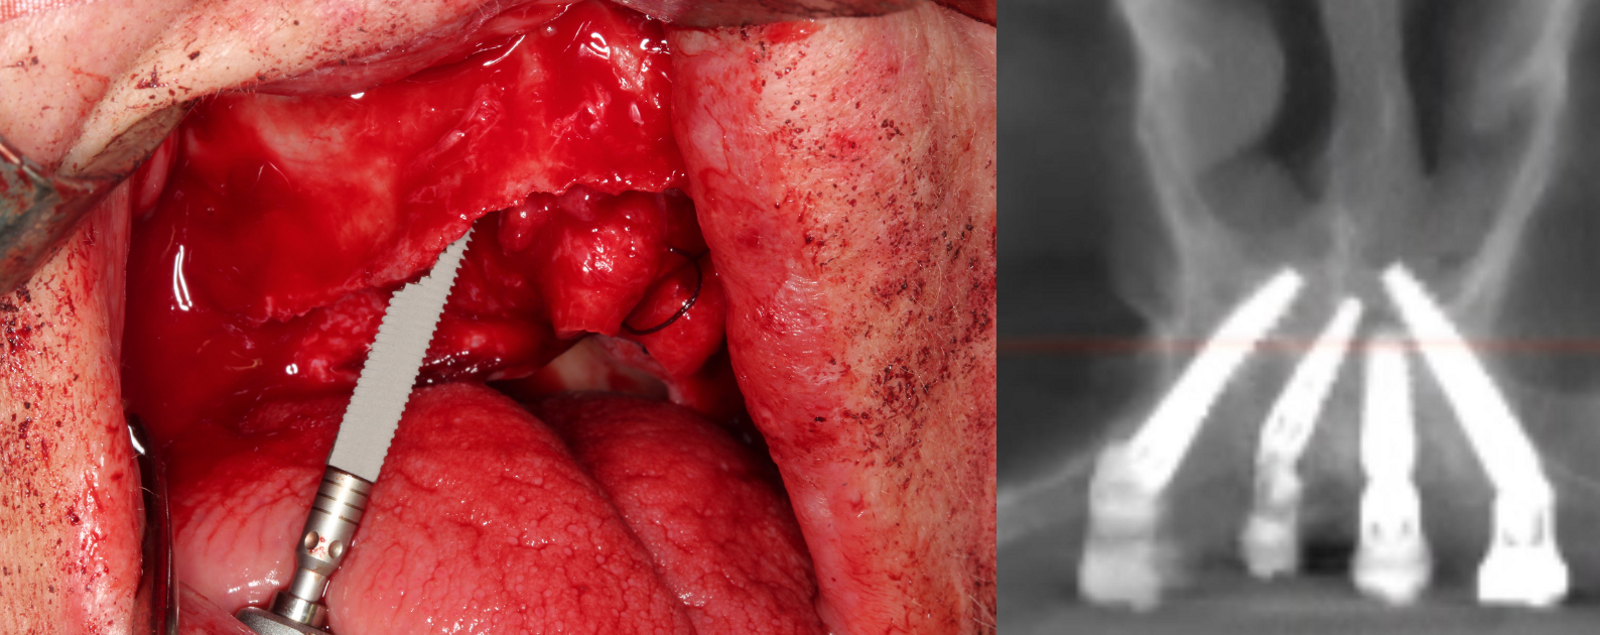

Implantaten met remote verankering onderscheiden zich van conventionele implantaten doordat het implantaat oppervlakte niet in zijn geheel procent in contact staat met het alveolaire bot. In tegenstelling tot het klassieke uitgangspunt dat het implantaat volledig omgeven moet zijn door bot, wordt bij remote verankering slechts het apicale deel van het implantaat in het zeer dense corticale basale bot verankerd, terwijl het coronale gedeelte van het implantaat langs de wand van de processus alveolaris, langs de sinus maxillaris wand, in een corticale fossa of zelfs deels met zacht weefsel in contact komt (figuur 1).

Een voorbeeld van implanteren via een palatinale benadering (palatal approach) bij een zeer ernstige horizontale geresorbeerde kaak (A). De implantaten bevinden zich apicaal geheel in dens nasale bot. Coronaal liggen de implantaten bloot aan de palatinale zijde en worden met dikke palatinale gingiva bedekt (B). Na 3 maanden zijn de multi-unit abutments omringd door gezonde gekeratinseerde gingiva (C).

Dit vormt in de praktijk geen nadeel zolang de primaire apicale stabiliteit hoog is, het coronale gedeelte goed bedekt wordt met een dik stuk aangehechte gingiva, de implantaten aan elkaar verblokt worden door een vaste prothetische voorziening en alle implantaten immediaat worden belast. De functionele stabiliteit komt voort uit de corticale grip van het ankerbot, vaak veel sterker dan de oorspronkelijke alveolaire structuur ooit was, en uit het verblokkingseffect van de implantaten aan elkaar om de buigkrachten tegen te gaan. Die eigenschap maakt zygoma-, pterygoïde, transnasale en transsinusale implantaten tot een betrouwbare oplossing bij ernstige atrofie in de bovenkaak.